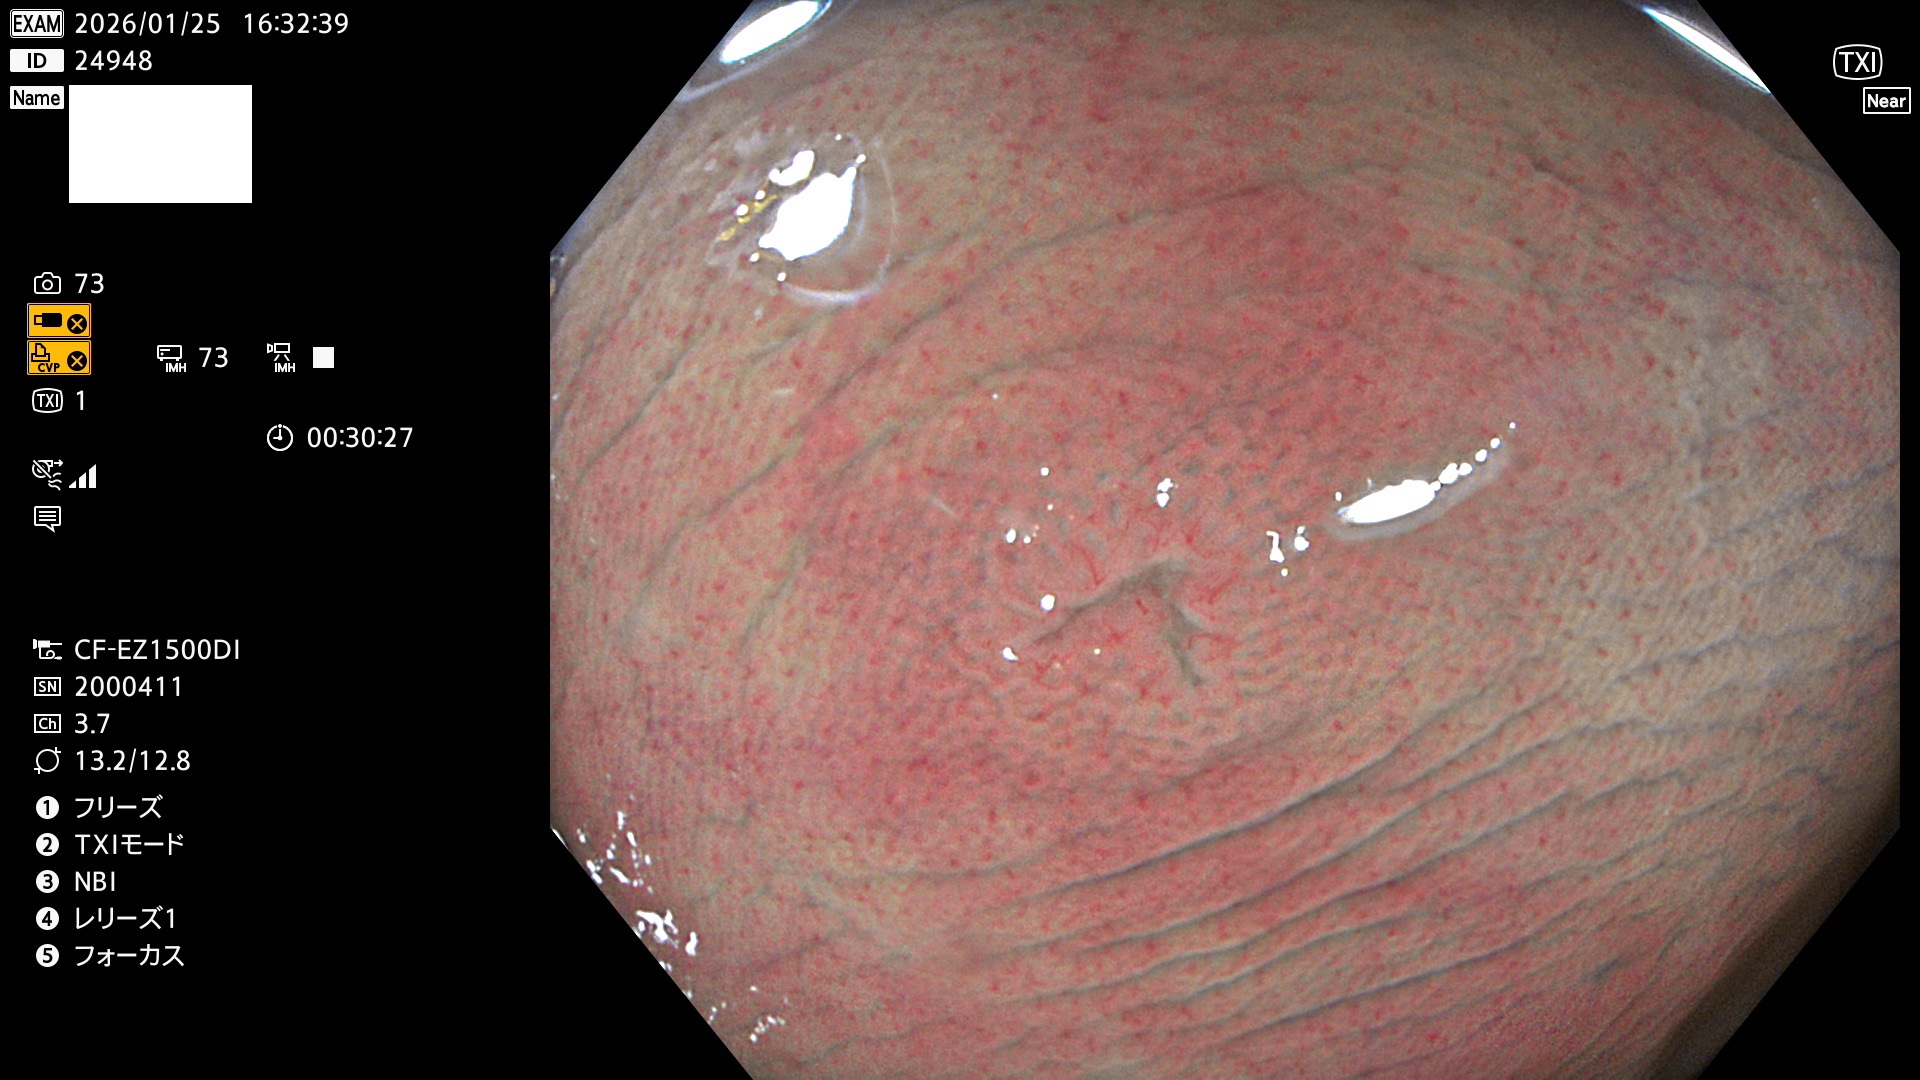

完全に平坦な物をUb、陥凹している物をUcと呼びます。Ubは認識が困難で、Ucはびらん(炎症)と紛らわしいために見落とされやすく、「内視鏡後・大腸癌」の原因になります。

専門的)Uc=De Novo癌? 内視鏡の解像度が低かった時代、このような説もありました。しかし今日の高精度内視鏡では良性の微小なUc型腺腫(APC遺伝子異常の腺腫)が日常的に見つかります。Ucこそが多段階発癌(Adenoma-Carcinoma Sequence)のMain Routeです。

毎週の検査(木・金・土・日)に発見されたUbとUc型・腺腫を、その週の日曜の夜にUPし1週間、提示します。

2026年1月22日〜1月25日の4日間(35件)4個 (Uc_ADR=4個/32人=13%)